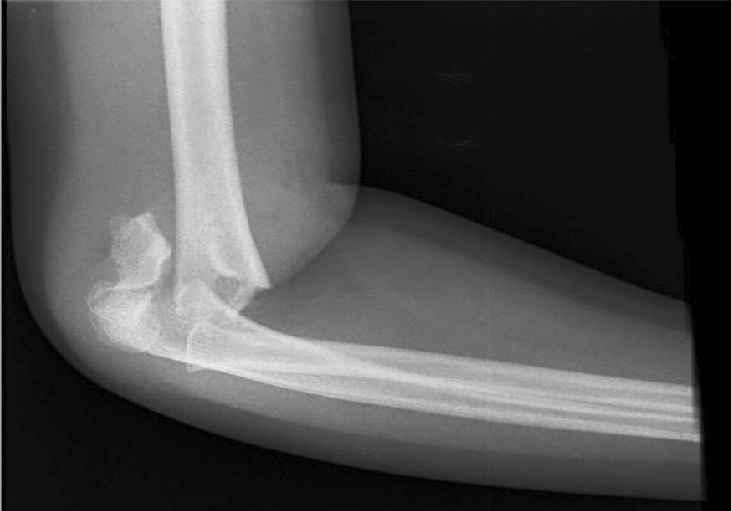

Fractura de Gartland desplazada: Las fracturas de Gartland son fracturas supracondíleas de húmero distal que ocurren en pacientes pediátricos (niños), estas pueden ser tratadas con un yeso o incluso necesitar cirugía para reducir y fijarla + un yeso.